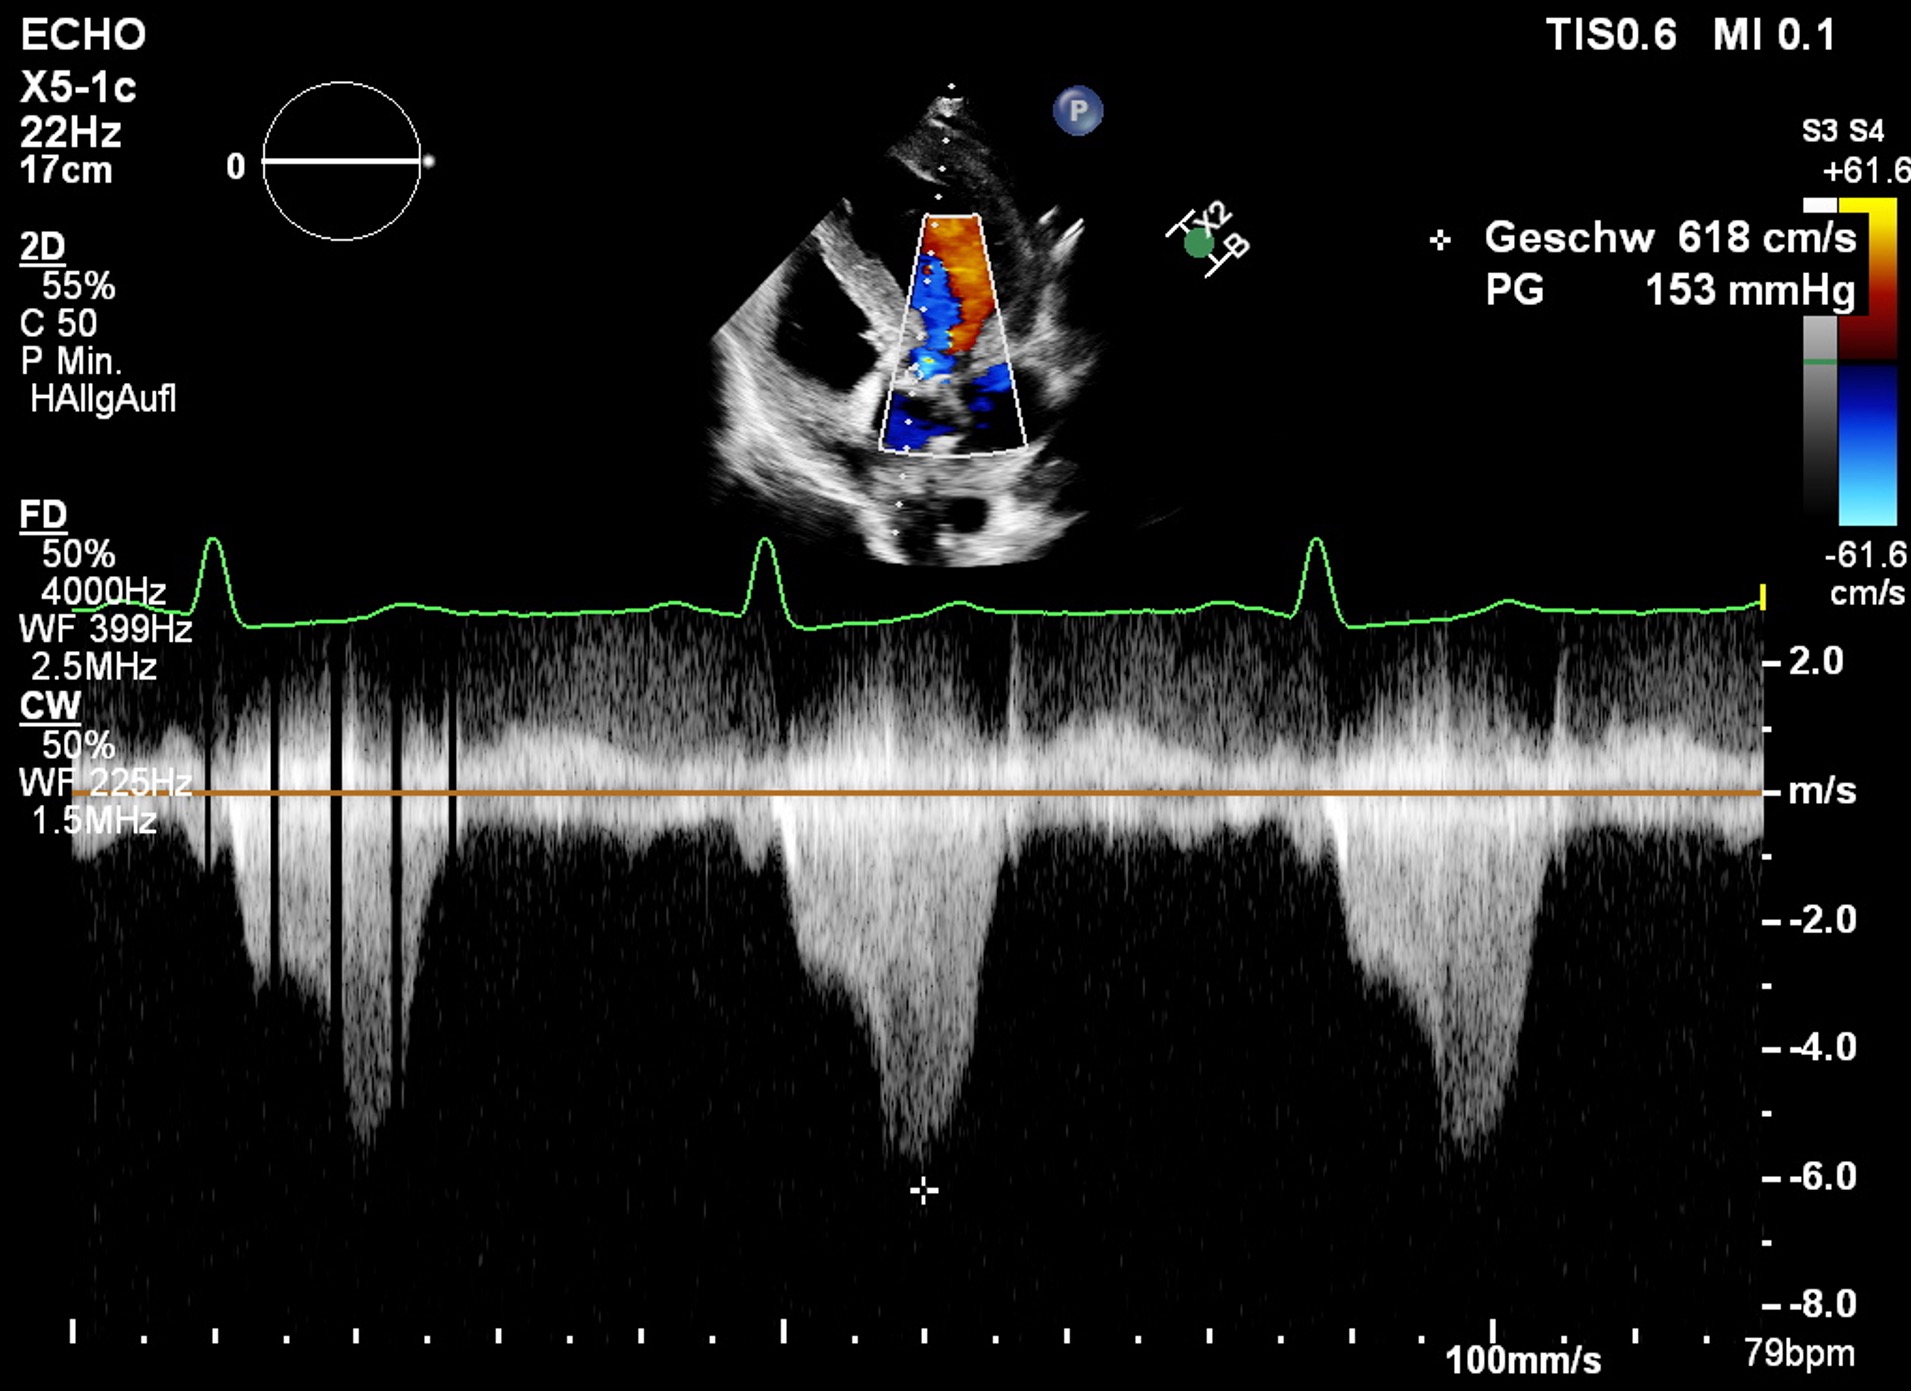

Die Echokardiografie ergab:

- basale Septumhypertrophie (16,5 mm)

- LVEF (Simpson biplan) 71 %

- hochgradige Mitralinsuffizienz (EROA 0,46 cm²)

- Gradient im LVOT in Ruhe 153 mmHg (= 6,2 m/s)